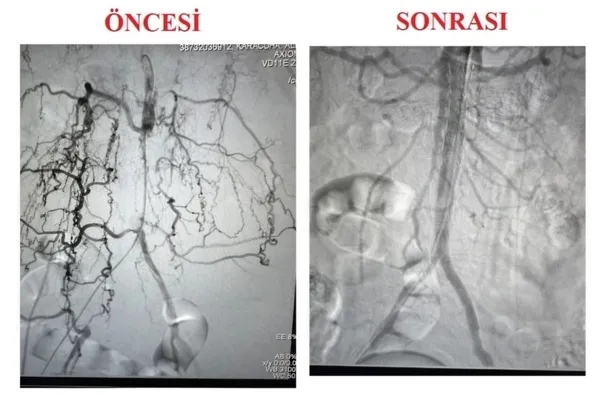

Trabzon'da 74 yaşındaki Osman Şen, yürüme mesafesinde kısalma ve yürüme ağrısı şikâyetleriyle Kanuni Eğitim ve Araştırma Hastanesi Kalp ve Damar Cerrahisi kliniğine başvurdu. Hastaya yapılan tetkikler sonucunda, karın içerisindeki aort damarı ve bacaklara giden damarlarında ciddi tıkanıklıklar tespit edildi. Hastanenin uzman ekibi tarafından açık cerrahinin yüksek risk taşıdığı hastalarda minimal invaziv bir seçenek sunan yeni bir tedavi yöntemi CERAB (Kaplı Stent ile Aortik Bifurkasyonun Endovasküler Rekonstrüksiyonu) tekniğini uygulamaya karar verdi. Bu yöntemle, hastanın karın içerisindeki aort damarı ve bacakları besleyen damarları yeniden yapılandırılarak kan akışı sağlandı.

Kanuni Eğitim ve Araştırma Hastanesi Kalp ve Damar Cerrahisi Uzmanı Op. Dr. Ali Fuat Karaçuha, "Aort damarı tıkanıklığı hastalığının tedavisinde geleneksel cerrahi yaklaşımlara uygun olmayan yüksek riskli hastalarda, endovasküler tedaviler minimal invaziv bir seçenek olarak önemli bir alternatif sunmaktadır. Greft stentlerin kullanılmasıyla yapılan bu teknik, hastalarda daha düşük morbidite ve mortalite oranlarıyla sonuçlanmakta, bu da tedavi başarısını artırmaktadır" dedi.

Kalp ve Damar Cerrahisi Uzmanı Op. Dr. İbrahim Düzcan ise, "CERAB tekniği, özellikle yaşlı ve cerrahi risk taşıyan hastalar için umut verici bir tedavi yöntemi. Osman Şen'in tedavisinde bu yeni yöntemi başarıyla uyguladık ve olumlu sonuçlar aldık. Bu tür yenilikçi teknikler, hastanemizin tedavi başarısını daha da artıracaktır" şeklinde konuştu.